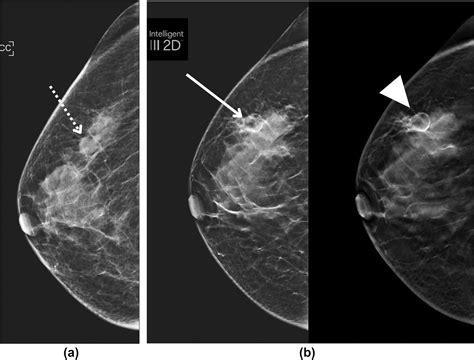

• Imaging Tests: Imaging tests such as mammography, ultrasound, or MRI may be used to visualize the affected tissue and rule out other conditions.